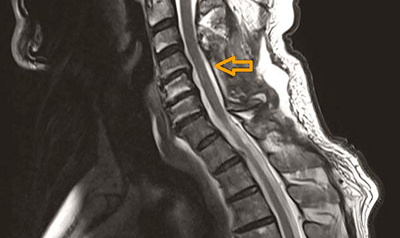

Abb. 1

MRI-Aufnahme eines 60-jährigen Patienten mit fortgeschrittener Einengung des Halswirbelkanals mit bereits eingetretener Schädigung des Rückenmarks des Halses (siehe Pfeil). Der Patient leidet an Schmerzen, Missempfindungen und Kraftlosigkeit in allen vier Extremitäten.